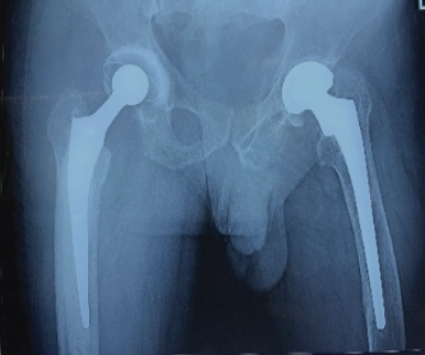

DEXA scan revealed no evidence of osteoporosis, and the patient underwent an oncological workup to rule out any metastatic cause for the pathological fracture. The patient subsequently underwent right cemented THR using the lateral approach. A cyst-like lesion was identified in the right femoral neck, which was excised and sent for histopathological examination. The patient’s post-operative radiograph was satisfactory (Fig. 3), and the patient was ambulated on the 1st post-operative day with support. The staples were removed after 2 weeks.

Figure 3: Post-operative radiograph showing cemented total hip replacement (right hip).